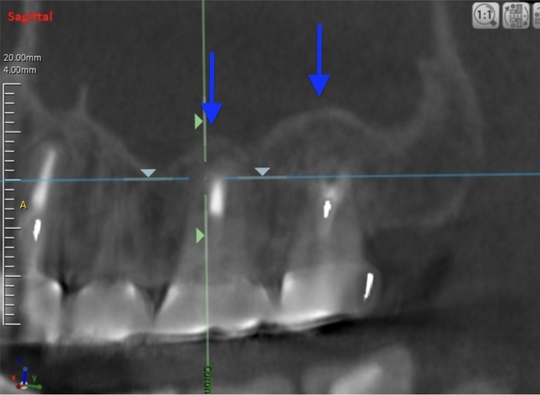

治療後

症状はすべて改善、経過3年後

根の周りが白っぽく骨ができています

骨の穴は完全に消えました